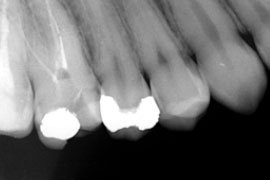

Aktuelle Röntgenbilder sowie eine symptombezogene Untersuchung des zu behandelnden Zahnes sind Grundlage für unsere Beratung über Prognosen der Therapie, Behandlungsalternativen sowie Behandlungskosten.

Entscheidend für den Erfolg der Wurzelkanalbehandlung ist die komplette Aufbereitung und Desinfektion des gesamten Wurzelkanalsystems. Die Aufbereitung der Kanäle bis an die Wurzelspitze erfolgt mit Stahl-Feilen, Ultraschall und hochflexiblen Nickel-Titan-Feilen. Dabei finden neben Handfeilen auch maschinelle Aufbereitungssysteme (drehmomentgesteuerte Feilen) ihre Anwendung. Die Bestimmung der Arbeitslänge erfolgt elektrometrisch und wird während der gesamten Therapie gemessen und kontrolliert.

Sehr lange, enge oder verzweigte Wurzelkanäle sind keine Seltenheit und die Desinfektion ist mit einem höheren Aufwand verbunden. Ein Dentalmikroskop, die elektrometrische Längenmessung, sowie ein Ultraschallgerät mit unterschiedlichen Arbeitsinstrumenten sind für den Erfolg der Behandlung wichtige Hilfsmittel.